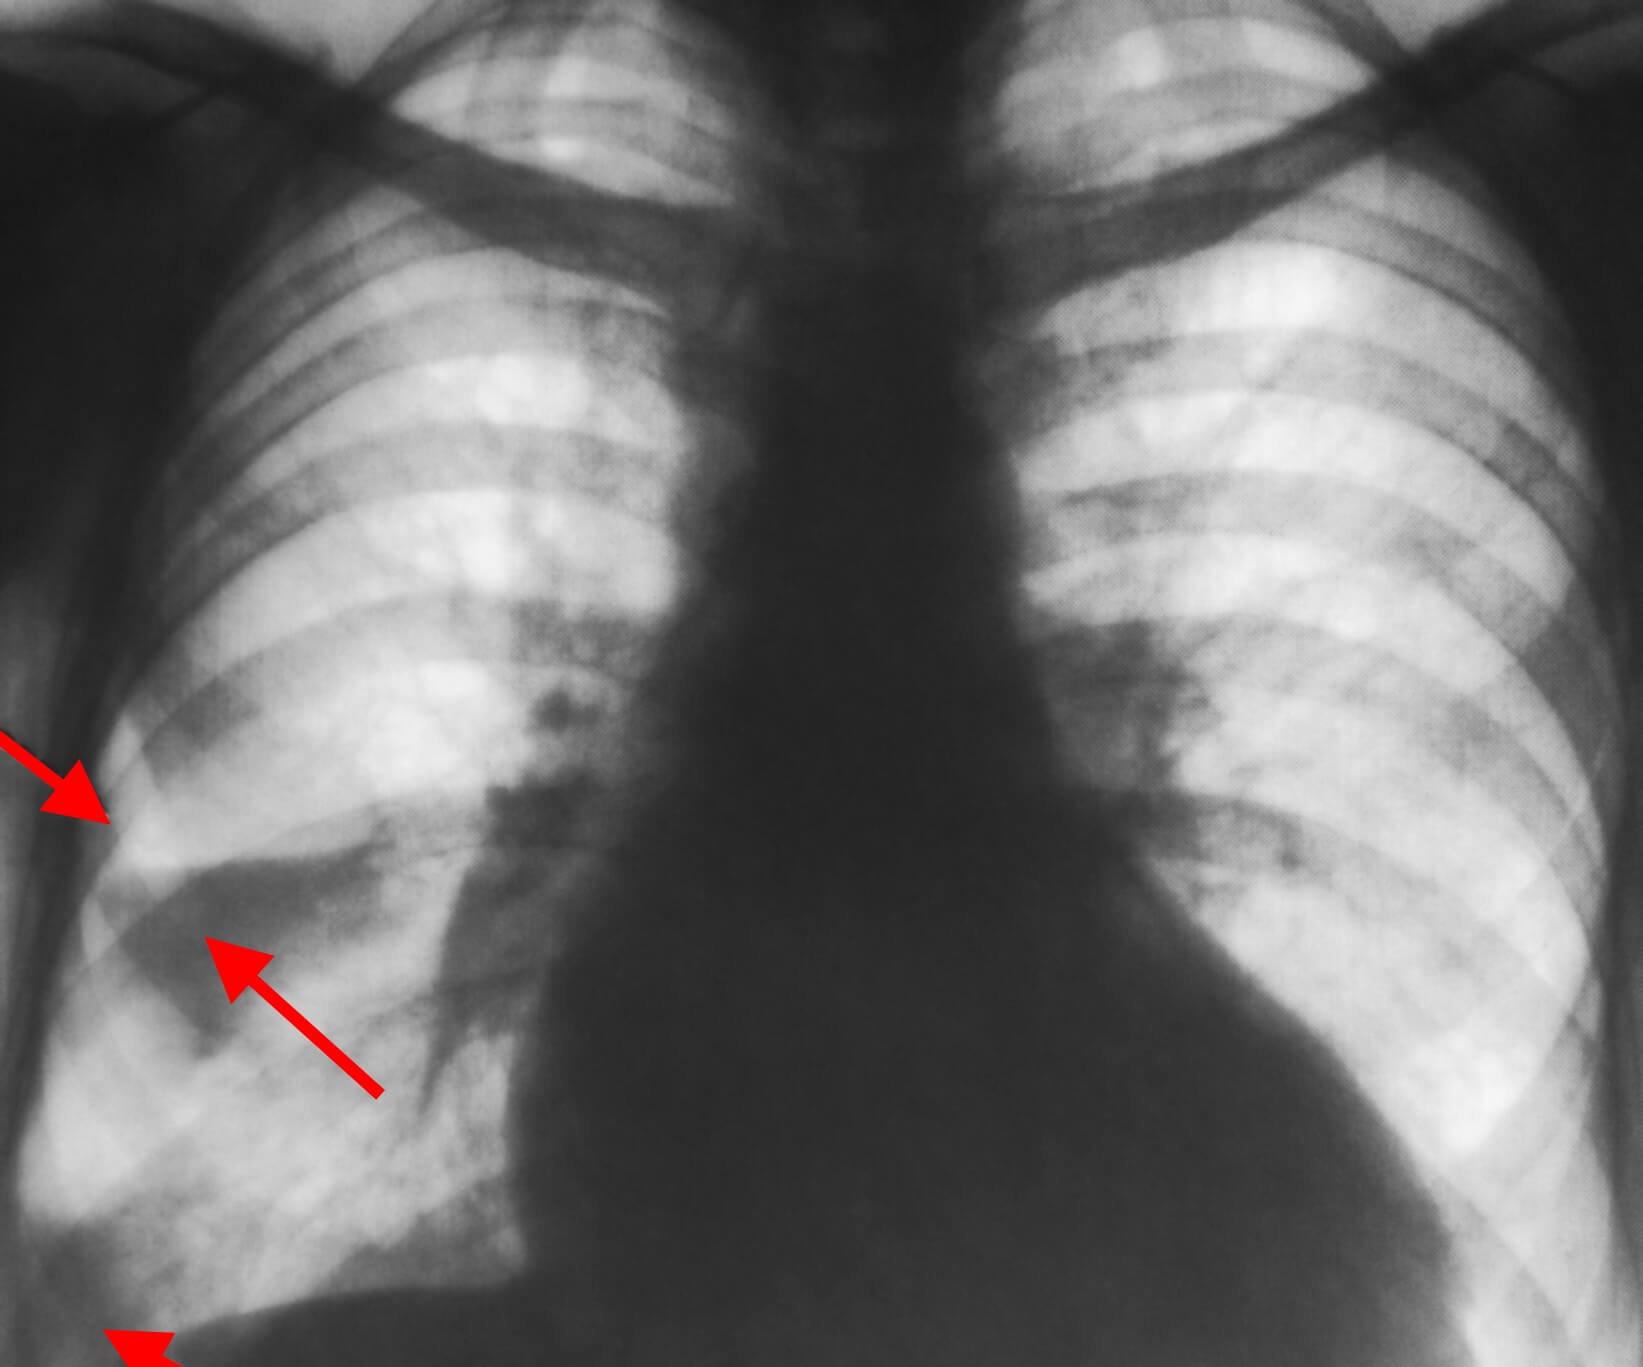

При инфаркте легкого информативным являются целый ряд инструментальных методов исследования – это:

- рентгенография легких в двух проекциях – на снимке можно увидеть тот самый «клин» легочной ткани, пострадавший от нехватки кислорода, а также жидкость в плевральной полости;